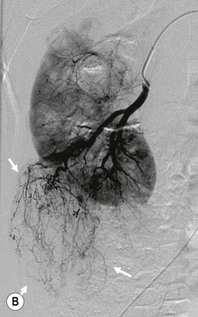

FMD